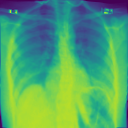

4.1.2 Lung Segmentation

Additionally, we evaluate the performance of DiffeoNN on real-world data, using a dataset with chest X-ray images and their ground-truth lung segmentation from (RSUA, 2023). The original dataset contains images and corresponding ground-truth segmentations into three different classes (“Non-Covid”, “Covid”, and “Non-Covid-Pneumonia”). We combine the images and corresponding ground-truth segmentations of the initial three classes into one dataset, which is then split into a training dataset of image-segmentation pairs, a validation dataset of pairs, and a test dataset of pairs. We then proceed as in Section 4.1.1 to create a dataset of diffeomorphically transformed images.

We apply DiffeoNN, the inner U-Net (naïve approach) and an augmented U-Net, which is trained on the original and the diffeomorphically transformed training dataset, to the diffeomorphically transformed images from the test dataset. Visual results are presented in Figure 4 and further details on the experimental setup, training, and additional examples in Appendix B. The results closely mirror those obtained on the synthetic dataset, see Table 1(b). On average, DiffeoNN outperforms the naïve approach, validating the effectiveness of our approach. The canonicalisation step pushes the input image towards the training dataset by moving the thorax to a more central position and aligning the shoulders, which makes it easier for the inner U-Net to predict an accurate lung segmentation. While our method performs slightly below the augmented gold-standard baseline, it offers more flexibility by not relying on data augmentation or retraining, making it a practical and robust solution in real-world applications.

| Input | Canonicalised Input | Segmentation of | Output DiffeoNN | Output Naïve U-Net | Output Augmented U-Net | Ground-Truth Segmentation |